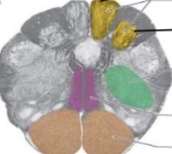

ventral horn

motor horn

dorsal horn

secondary sensory neurons